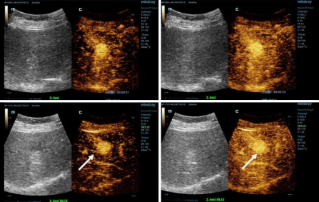

![more-precise-diagnoses-with-hifr-ceus.thumb.319.319 HiFR CEUS ile Daha Kesin Tan?lar]() HiFR CEUS ile Daha Kesin Tan?larKontrastl? ultrason (CEUS) ?ok dinamik bir aland?r ve son birka? y?lda teknolojik yenilikler g?rû¥ntû¥ kalitesini daha da art?rm??t?r. Bu yeniliklerden biri, ayn? anda geleneksel ultrasona g?re on kata kadar daha fazla g?rû¥ntû¥ û¥retebilen yû¥ksek ?er?eve h?zl? kontrastl? ultrasondur (HiFR CEUS).Ultrason | Genel g?rû¥ntû¥leme 2022-12-16

HiFR CEUS ile Daha Kesin Tan?larKontrastl? ultrason (CEUS) ?ok dinamik bir aland?r ve son birka? y?lda teknolojik yenilikler g?rû¥ntû¥ kalitesini daha da art?rm??t?r. Bu yeniliklerden biri, ayn? anda geleneksel ultrasona g?re on kata kadar daha fazla g?rû¥ntû¥ û¥retebilen yû¥ksek ?er?eve h?zl? kontrastl? ultrasondur (HiFR CEUS).Ultrason | Genel g?rû¥ntû¥leme 2022-12-16 -